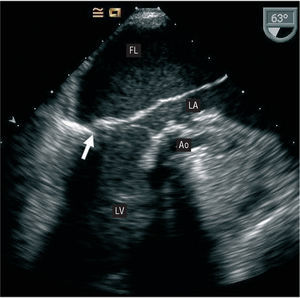

During the immediate postoperative period, the patient experienced hemodynamic instability and difficulty weaning from the intra-aortic contrapulsation balloon. On transthoracic echocardiography, the mitral prosthesis showed no alterations and left ventricular systolic function was preserved. Because there was no correlation between the transthoracic echocardiography findings and the patient's clinical status, transesophageal echocardiography was performed. The examination revealed a false chamber in the interior of the left atrium that was formed by the dissected posterior atrial wall and occupied nearly the entire true lumen (Figure 1). In addition, retrograde systolic flow was observed in the interior, coming from the posterior wall of the left ventricle below the prosthesis. There was no evidence of a communication between the true and false lumen, or perivalvular regurgitation (Figure 2).

Figure 1.